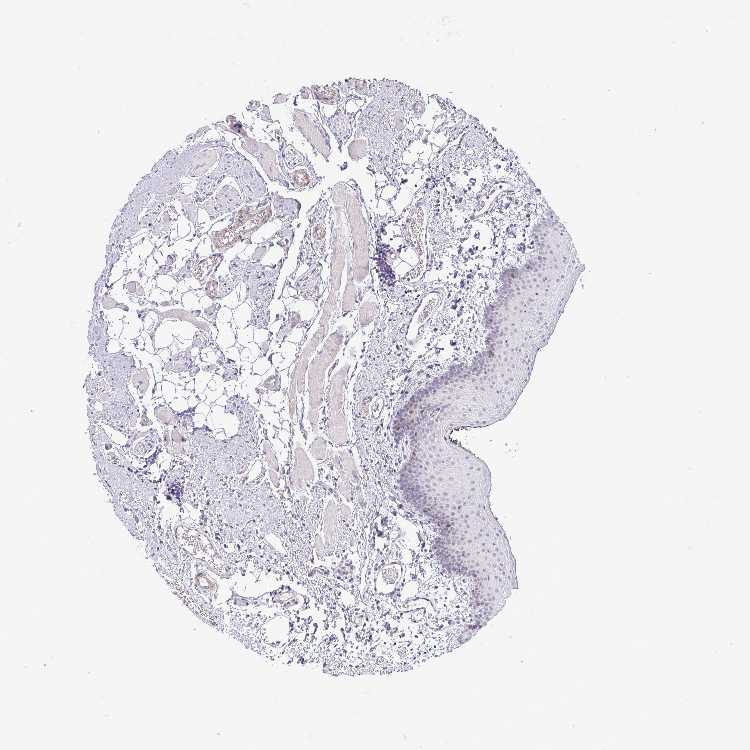

TISSUE PRIMARY DATA ORAL MUCOSA Show tissue menu

ORAL MUCOSA - Antibody stainingi

Antibody staining in the annotated cell types in the current human tissue is reported as not detected, low, medium, or high, based on conventional immunohistochemistry profiling in selected tissues. This score is based on the combination of the staining intensity and fraction of stained cells.

Each image is clickable and will lead to virtual microscopy that enables deeper exploration of all samples and also displays staining intensity scores, fraction scores and subcellular localization as well as patient and tissue information for each sample.

Antibody HPA057150Antibody CAB015228

Squamous epithelial cells LowMedium